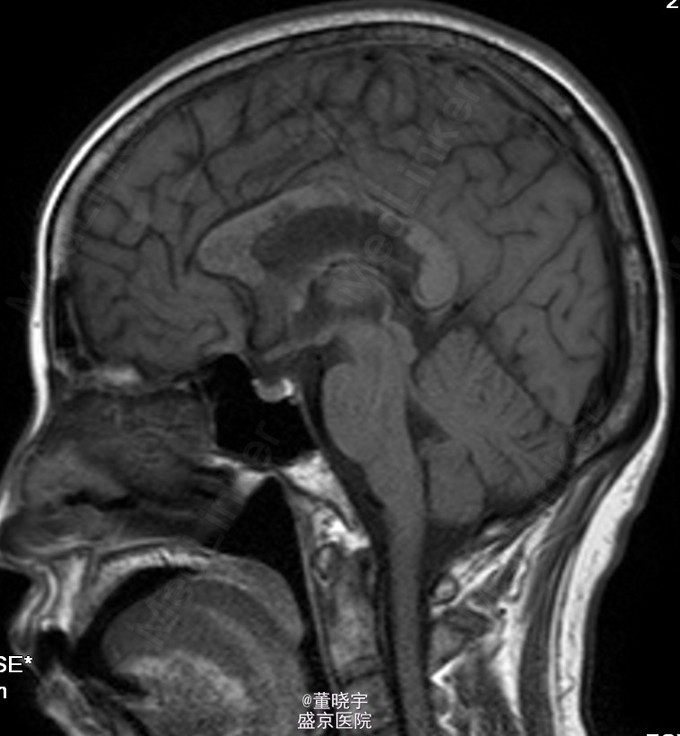

神经系统专科查体:神清语明,双瞳等大正圆,D=4.0mm,对光反射迟钝,视力丧失,双眼球各向运动充分,无复视及眼震,额纹对称,双侧鼻唇沟对称,伸舌居中,转颈有力,四肢肌力Ⅴ级,肌张力正常,双上肢指鼻准确,双下肢跟膝胫试验稳准,BCR L++R++, TCRL++R++,PSRL++R++,Babinski征L+R+,Hoffmann征L-R-,颈强,双掌颏反射(+)。 辅助检查:腰穿压力200mmH2O,细胞总数28*10^6/L,白细胞24*10^6/L,氯化物118.0mmol/L,糖2.41mmol/L,蛋白2.1g/L。 视觉诱发电位:双侧视通路传导障碍。 颅脑MRI见上。 核抗体(ANA)阳性;抗SS-A及抗SS-B抗体均阳性;IgG、IgA升高;补体 C3、C4下降。

诊断:原发性干燥综合征合并中枢损害 处理:静脉点滴丙种球蛋白治疗,临床症状稳定后出院口服强的松片10毫克/天。

半年后患者再次入院复诊,复查颅脑MRI提示新增病灶,但风免相关化验未见改变,急性长期口服激素治疗。 讨论:原发性干燥综合症(pSS)是一种以唾液腺和泪腺腺体淋巴细胞浸润和破坏为特点的自身免疫性疾病,临床主要表现为眼干、口干。腺体外表现主要是由于类似的单核细胞浸润或血管炎引起。CNS-SS的发病率及其颅脑MRI表现目前仍存在争议,有文献报道CNS病变发生率为0%-60%[1]。既往的一个400例患者大样本研究发现,只有1%患者合并CNS并发症。 CNS-SS的临床表现多样,脑部病变包括局灶性和弥漫性病变,局灶性病变主要表现为局部感觉和运动异常、失语、癫痈发作、构音障碍和视觉减退等;弥漫性病变主要表现为亚急性或急性脑病、无菌性脑膜脑炎、心理障碍和认知障碍等。中枢神经系统病变多隐匿起病,少部分患者呈急性或亚急性起病,部分患者同时合并有周围神经系统损害,加上部分pSS患者以中枢神经系统损害为首发症状,使得临床症状表现多样,诊断困难,极易误诊、漏诊并延误治疗。 目前对于pSS合并中枢神经系统病变治疗还没有统一的方案,大剂量激素治疗是目前临床中常用的方法之一,也有报道对于激素效果不佳的患者合并应用环磷酰胺也收到了不错的效果。静脉注射丙种球蛋白(IVIg)也是免疫相关的中枢神经系统病变常用治疗手段之一,尽管外文报道IVIg对于pSS引起的周围神经病变效果明显。